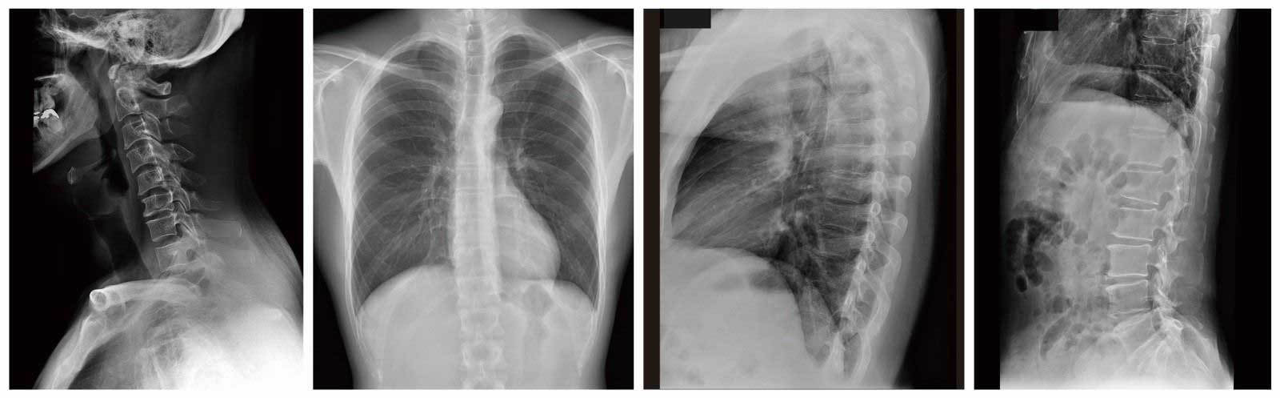

„REALISM“ ist eine Bildverarbeitungs-Engine, die entwickelt wurde, um die Bildqualitätsleistung von AeroDR Detektoren mit hochauflösenden Pixeln und hoher DQE zu maximieren. Dank seiner verbesserten Frequenzverstärkungsverarbeitung kann es sowohl niedrige als auch hohe Frequenzbereiche originalgetreuer darstellen und realistische Bilder von feinen Strukturen wie Knochenbälkchen und dicken Körperteilen (Niedrigdosisbereiche) erzeugen.

Beibehaltung des Kontrasts bei gleichzeitig klarerer Darstellung des gesamten Bildes

Mit verbesserter Dynamikbereichskompressionsverarbeitung und neu eingeführter LUT werden stereoskopische Bilder bereitgestellt, indem einzelne Strukturen von Niedrigdosis- bis zu Hochdosisregionen ausgedrückt werden.

Mit seiner hohen Auflösung von 100 μm bietet der AeroDR 3 Detektor die vierfache Pixelanzahl (3.488 × 4.256) gegenüber der Standardauflösung von 200 μm.

Damit können selbst kleinste Strukturen auf den Röntgenbildern entscheidend vergrößert werden. Dadurch wird die Qualität der Diagnose erheblich gesteigert, da dafür Bilddetails und Dosiseffizienz von entscheidender Bedeutung sind.